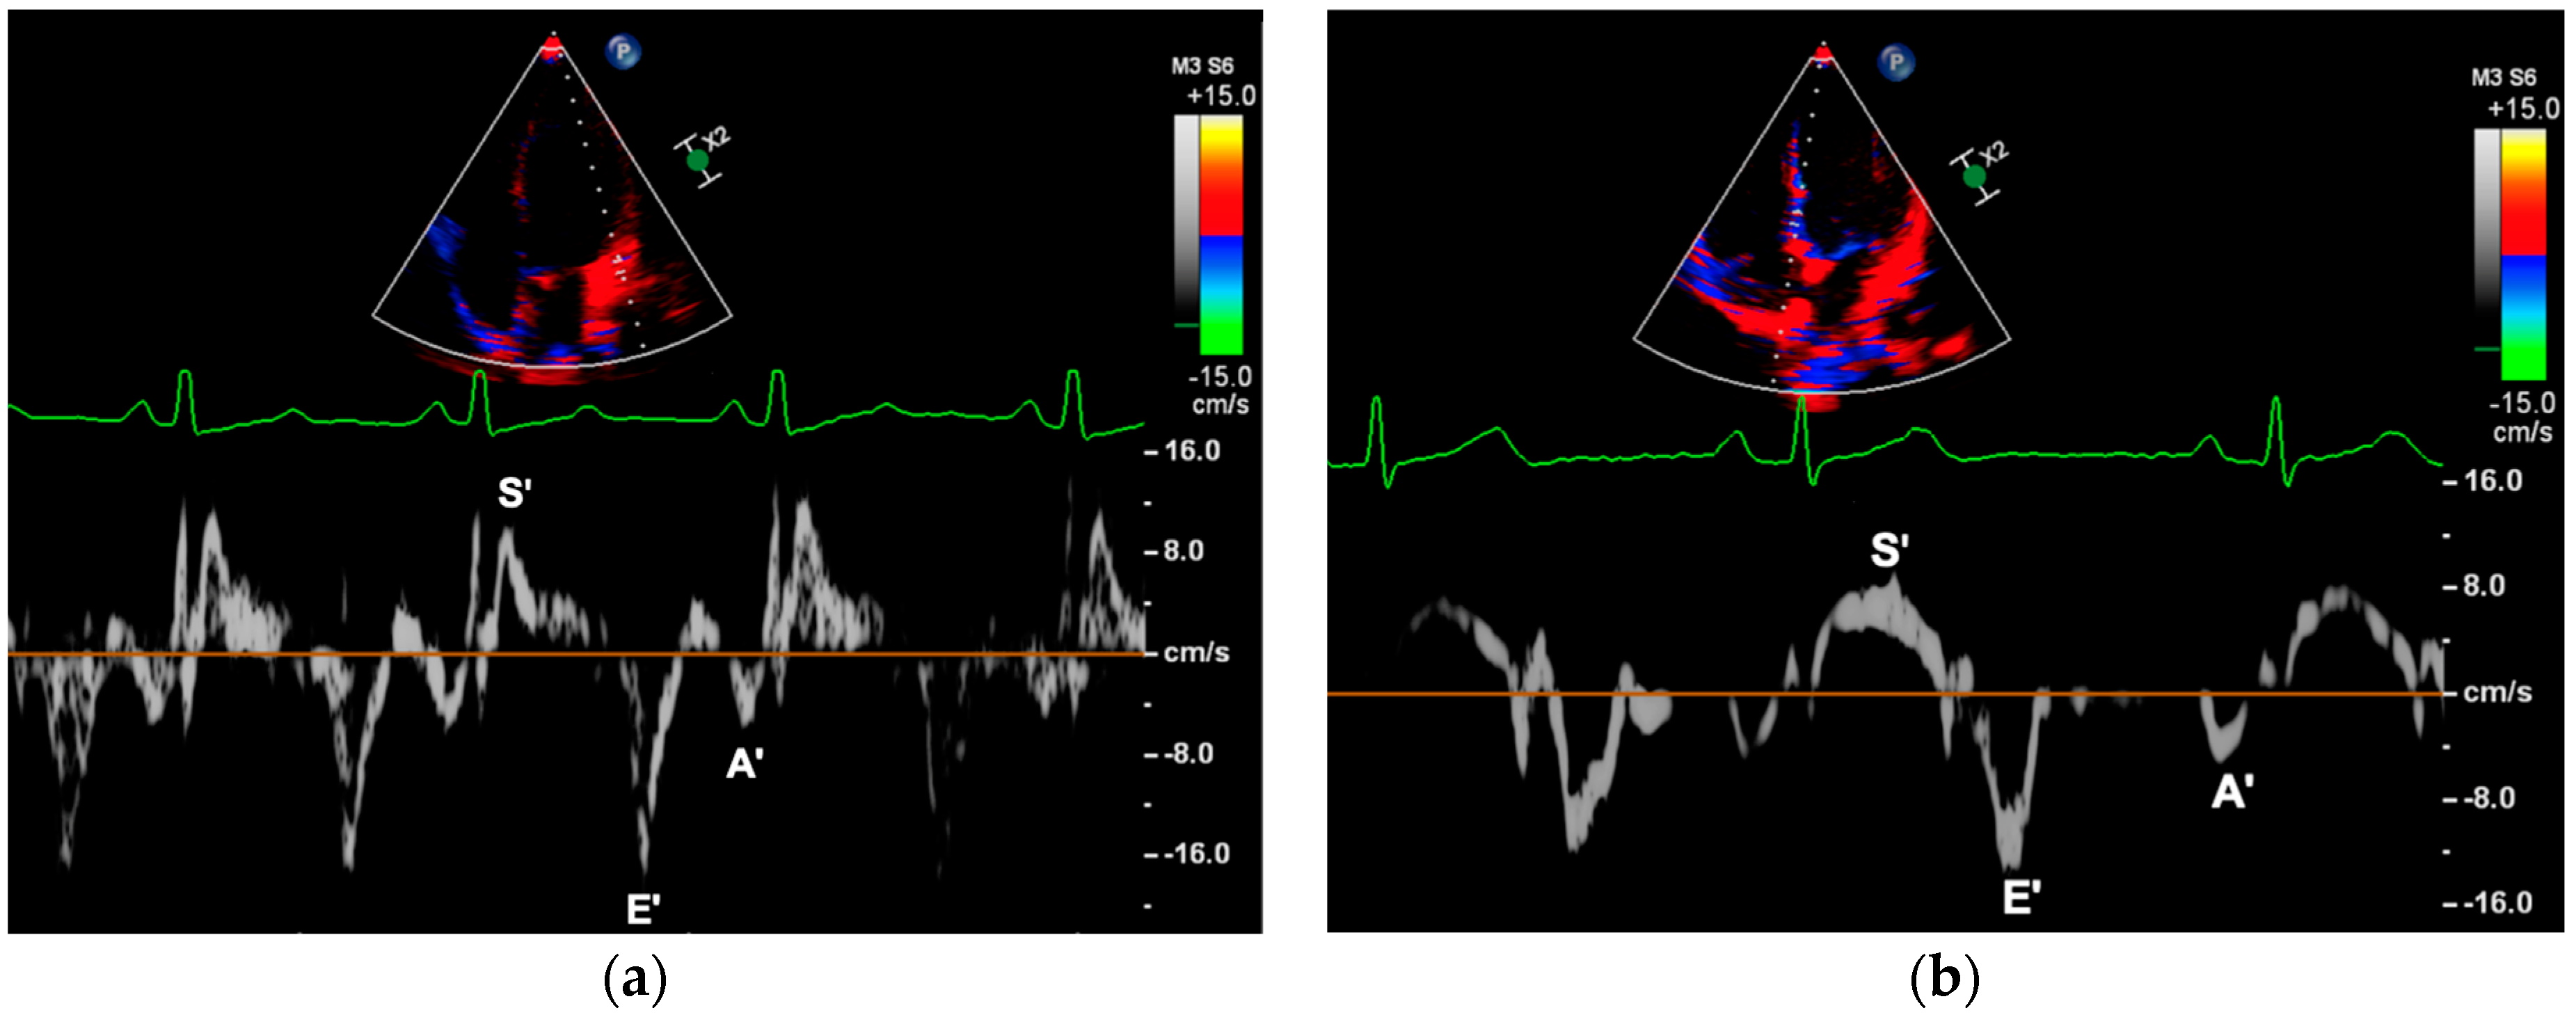

2.3.3. Myocardial Peak Velocities

| Tissue Doppler Imaging | ||||

| S’RV (cm/s) 1 | 12.27 ± 1.78 | 12.67 ± 2.09 | 0.222 | 0.261 |

| E’RV (cm/s) 2 | 14.51 ± 2.92 | 14.62 ± 2.77 | 0.833 | >0.999 |

| A’RV (cm/s) 3 | 8.31 ± 2.09 | 8.63 ± 3.20 | 0.511 | 0.774 |

| S’LV (cm/s) 4 | 11.48 ± 2.33 | 10.99 ± 2.84 | 0.253 | >0.999 |

| E’LV (cm/s) | 20.67 ± 3.78 | 19.29 ± 3.29 | 0.020 * | 0.552 |

| A’LV (cm/s) | 7.68 ± 2.47 | 7.05 ± 2.00 | 0.095 | 0.894 |

| S’IVS (cm/s) | 7.62 ± 1.10 | 7.61 ± 1.17 | 0.972 | >0.999 |

| E’IVS (cm/s) | 13.68 ± 1.77 | 13.14 ± 1.93 | 0.076 | >0.999 |

| A’IVS (cm/s) 5 | 5.45 ± 1.25 | 5.03 ± 1.32 | 0.057 | 0.312 |

| E/E’LV | 4.96 ± 1.01 | 5.22 ± 0.95 | 0.099 | >0.999 |

| E/E’IVS | 7.40 ± 1.30 | 7.63 ± 1.28 | 0.279 | >0.999 |

| E/E’AVG | 6.18 ± 0.96 | 6.43 ± 0.89 | 0.105 | >0.999 |